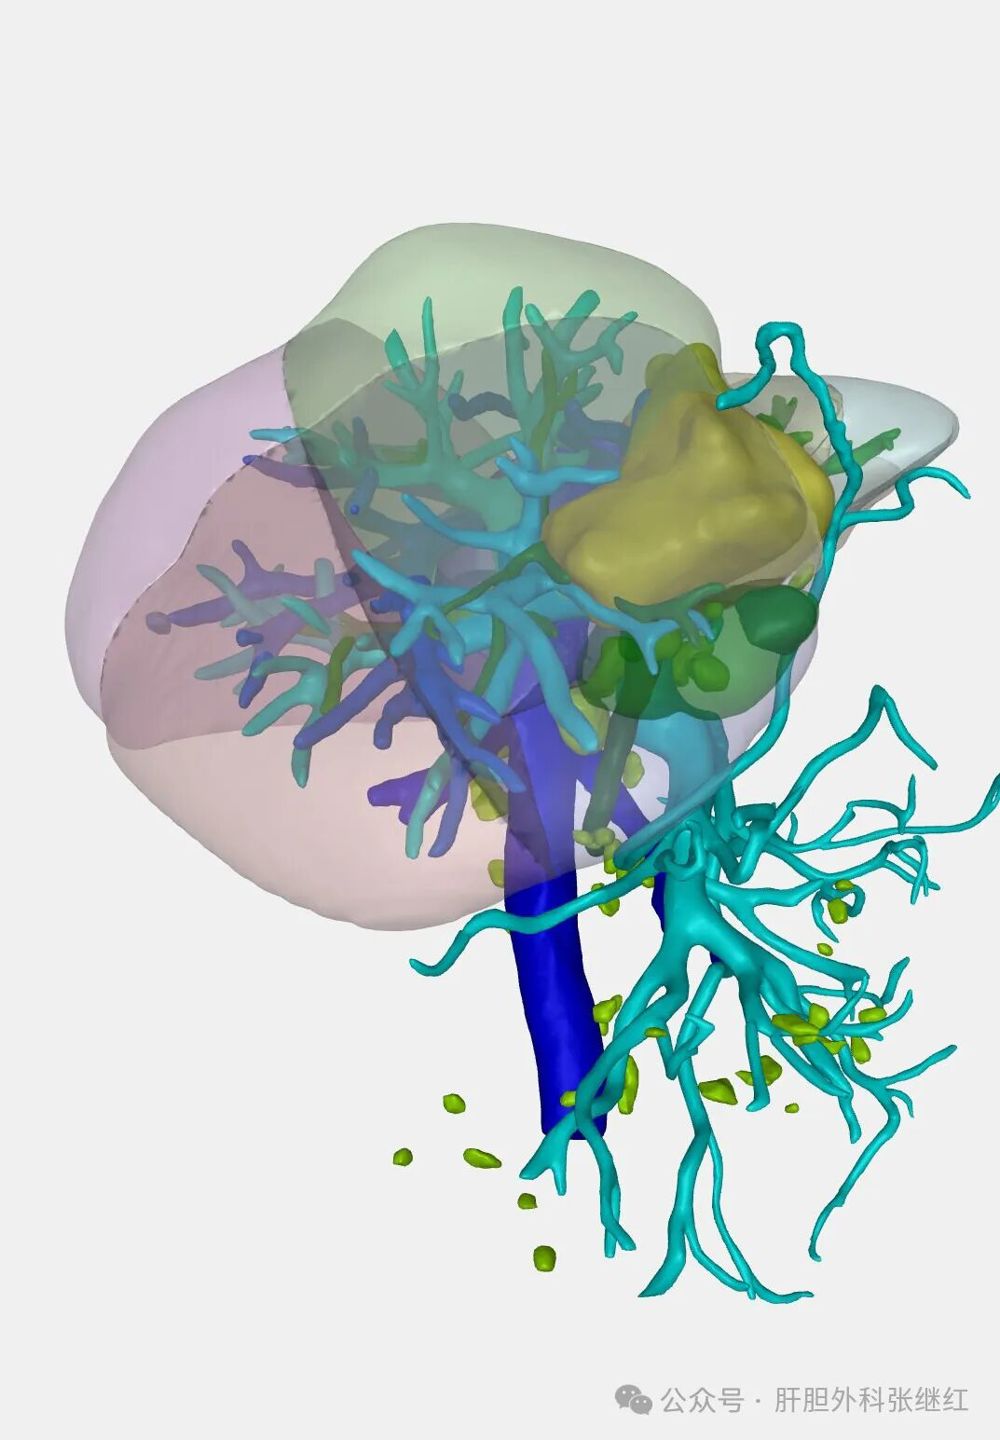

手术前三维重建